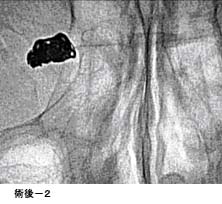

(3)頸動脈狭窄症に対するステント留置術

(現在、ステントは保険適応となっておりません。)